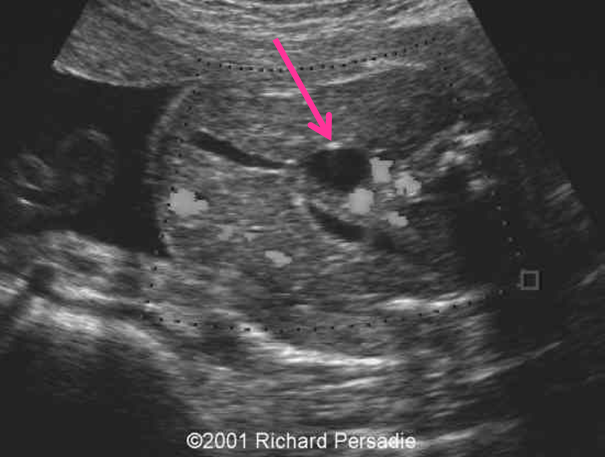

duodenal atresia